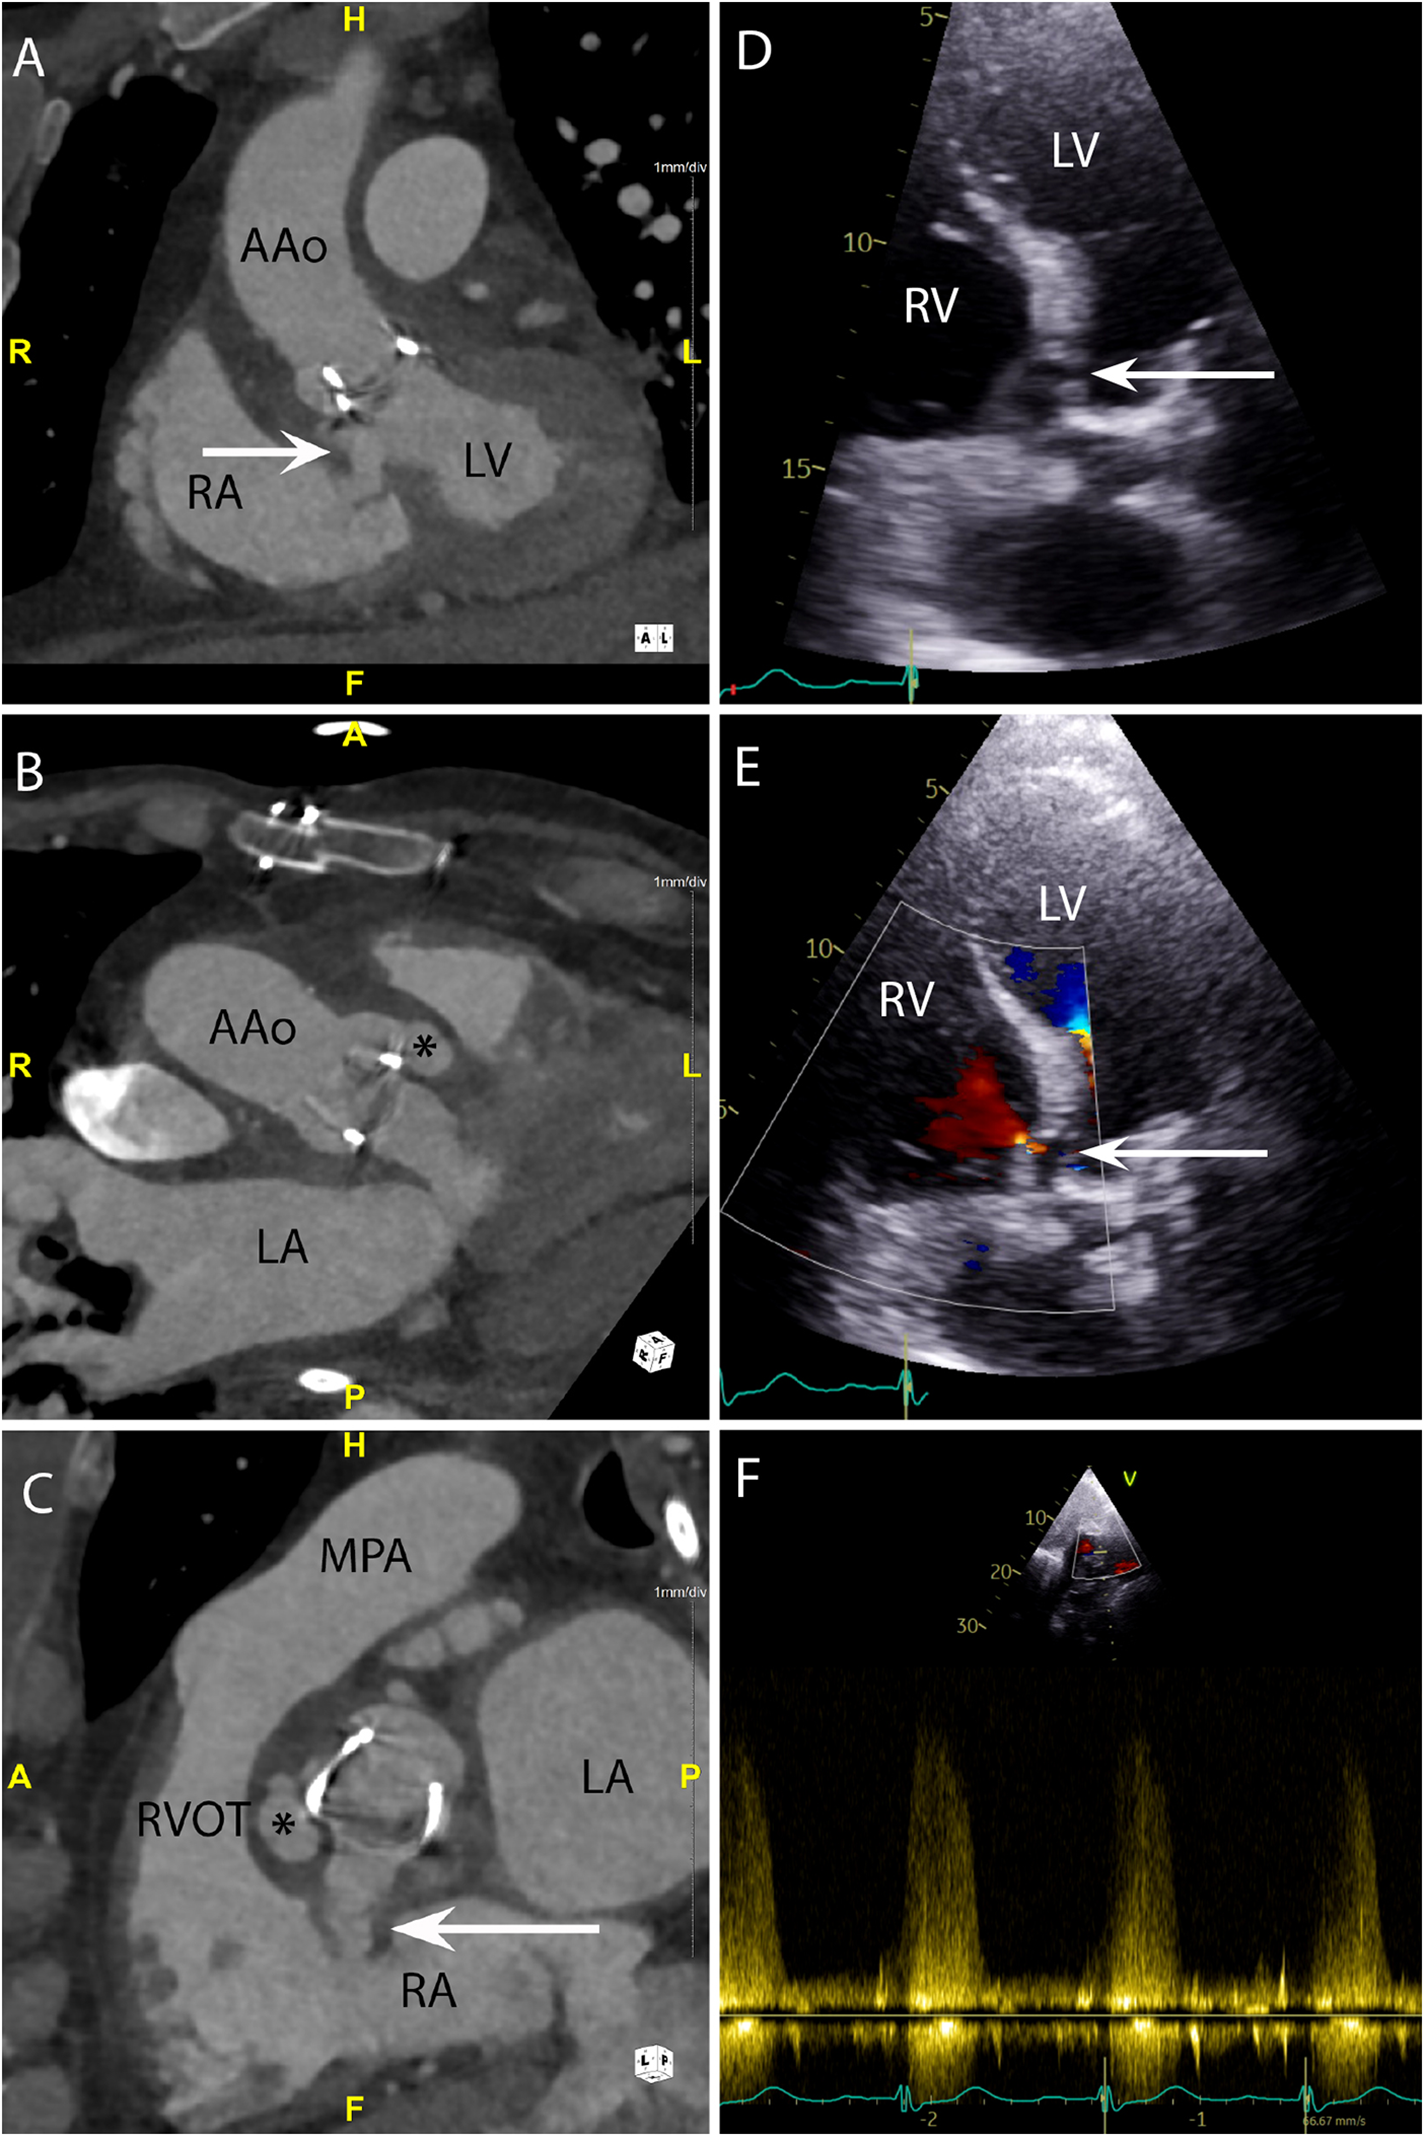

CASE 6 - A 71-year-old man presented with fever, confusion and fatigue. Enterococcus faecalis was isolated from blood cultures (see text). RA, right atrium; RVOT, right ventricular outflow tract; RV, right ventricle; MPA, mean pulmonary artery; LA, left atrium; LV, left ventricle; AAo, ascending aorta.

A 71-year-old man presented with fever, confusion and fatigue. Enterococcus faecalis was isolated from blood cultures. Cardiac CT was performed: An oblique coronal (Figure 6A) view demonstrated a paravalvular fistula (arrow) extending from the region of the aortic valve non-coronary cusp (NCC) and left ventricular outflow tract into the right atrium (RA). An oblique axial view (Figure 6B) demonstrated a pseudoaneurysm (asterisk) (HU 283) originating from the right coronary cusp (RCC). An oblique in-plane view (Figure 6C) demonstrated both the pseudoaneurysm (asterisk) originating from the RCC and the fistulous connection (arrow) between the NCC and RA. Preceding TTE images in the apical 5-chamber view (Figure 6D) demonstrated a likely communication between the aortic valve and LVOT. Blood flow through this communication was documented with both apical 5-chamber colour Doppler (Figure 6E) and subcostal 4-chamber pulsed wave Doppler (Figure 6F). A subsequent CT was performed to delineate the fistulous connections more definitely. The CT scan also confirmed a small anterior aortic root pseudoaneurysm that had not been suspected on the TTE.